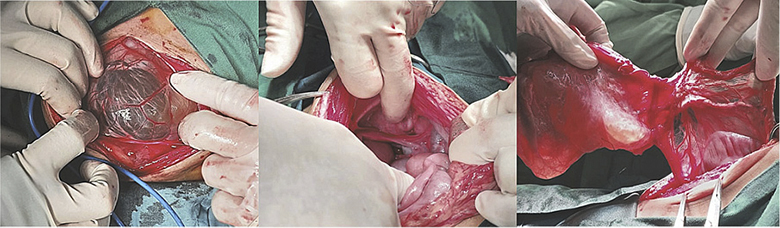

Figure 3. Intraoperative finding showing omental cyst, the origin, and the cyst wall

It was determined by anamnesis, physical examination, and imaging that the diagnosis was an ovarian cyst. As we continue laparotomy with midline incision from obstetrics department, we revealed a 8x8x10 cm sized cystic mass within the left transverse colon omentum, uterus and both ovaries were normal (Figure 3). We excised the cyst in toto and omentectomy then sent for pathological anatomy and cytology analysis. Instead of an ovarian cyst, we found an omental cyst during the operation (Figure 4), thus we had to conduct an excision and omentectomy and postoperatively achieved favorable results. Pathological examination revealed findings a inclusion cyst containing connective tissue, fat, and muscle. Cytology findings are suggestive for transudative effusion from the cyst and the international system for reporting serous fluid (ascites) cytopathology negative for malignancy (Figure 5). She was discharged three day after.